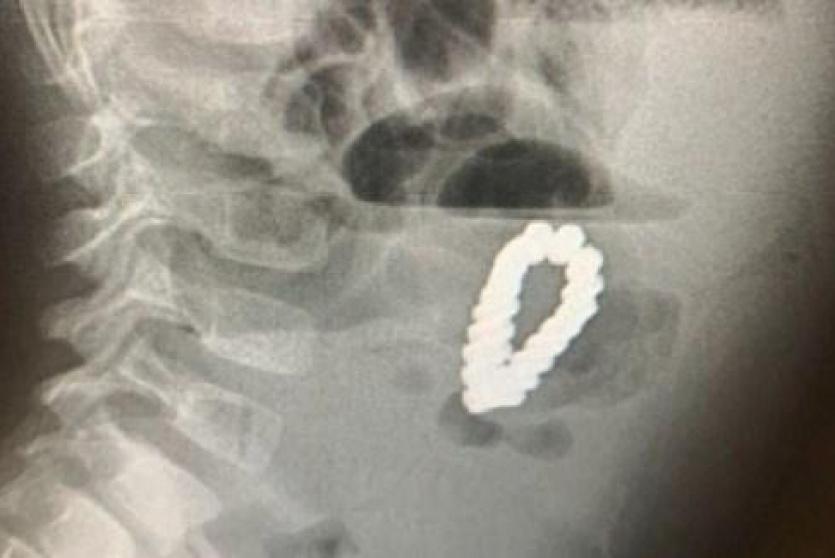

وقالت مجلة Paediatric Surgery Case Reports الأمريكية إن الأطباء أصيبوا بالحيرة، عندما كشفت عمليات المسح أن الطفل البالغ من العمر 4 سنوات كان يحمل بداخله سواراً مغناطيسياً.

ورغم إزالة الزائدة الدودية استمرت آلام الطفل، وعندما أجرى الأطباء عمليات المسح، كانوا مندهشين لرؤية شيء على شكل سوار داخل بطن الطفل، وكان والداه مرتبكين بنفس القدر.

وبشكل لا يصدق، يعتقد الأطباء أن الصبي قد ابتلع كل حبة مغناطيسية على حدة خلال مدة غير معروفة، ولكن بسبب خصائصها المغناطيسية، فقد تمكنت من الالتصاق ببعضها البعض مشكلة حلقة، ووصلت إلى حد سد أمعاء الصبي وحتى حفر ثقوب في أمعائه.

وأجرى الجراحون على الفور عملية فتح البطن على الطفل لإزالة 18 قطعة مغناطيسية سداسية الشكل، ثم سارعوا لإصلاح الضرر الذي لحق بأمعائه.